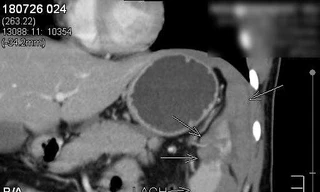

TPO - Các bác sỹ Bệnh viện Sản nhi Bắc Giang đã phẫu thuật thành công cứu sống bé Nông Minh Khôi (8 tuổi, trú tại xã Yên Bình, huyện Hữu Lũng, tỉnh Lạng Sơn) nhập viện trong tình trạng vô cùng nguy kịch do bị vỡ lách độ 4.